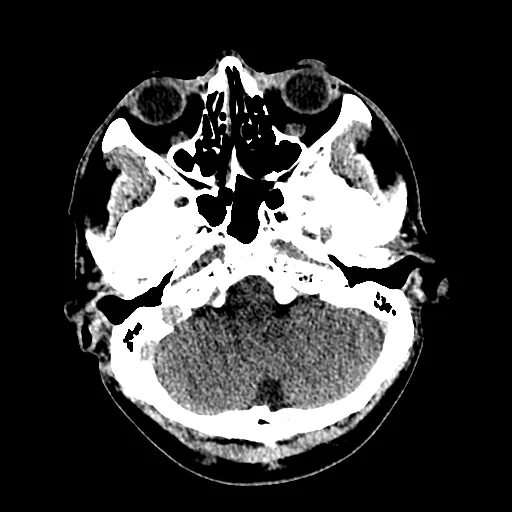

Мрт головного мозга мосто мозжечкового угла